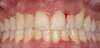

Cas 2

Une jeune patiente d’une trentaine d’année vient consulter pour des « brûlures » gingivales. Elle est très fatiguée et dit avoir très mal. Elle déclare fumer beaucoup et se dit stressée. L’examen cliniques montre des papilles gingivales « décapitées». Le diagnostic de GUN s’impose très vite.

Un traitement antibiotique à base de doxycycline et un brossage à l’eau oxygénée en plus de l’utilisation du fil dentaire, permet en un mois de retrouver un calme clinique, même si l’aspect gingival est encore inflammatoire.

Au bout de deux mois, l’aspect gingival est satisfaisant. Il est fortement recommandé d’abandonner le tabac.